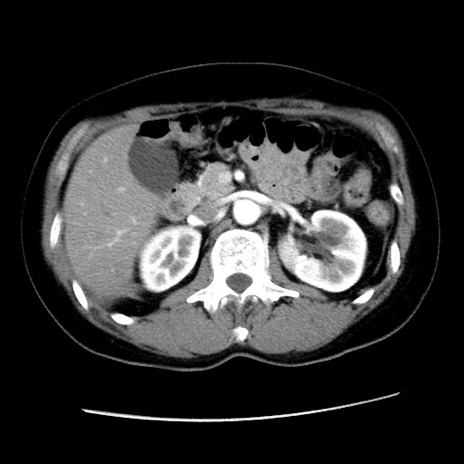

症例10(横断像)

【症例】 50歳代女性

【主訴】 腹痛

【現病歴】前日生レバーを食べた。今朝に排便あり。 昼前に突然発症の腹痛を生じ、当院救急外来を受診した。

【既往歴】 子宮筋腫にてで子宮全摘後

【身体所見】 意識清明、腹部:平坦、軟、下腹部やや左を中心に圧痛・反跳痛あり、筋性防御あり

【データ】WBC 7800、CRP 0.07